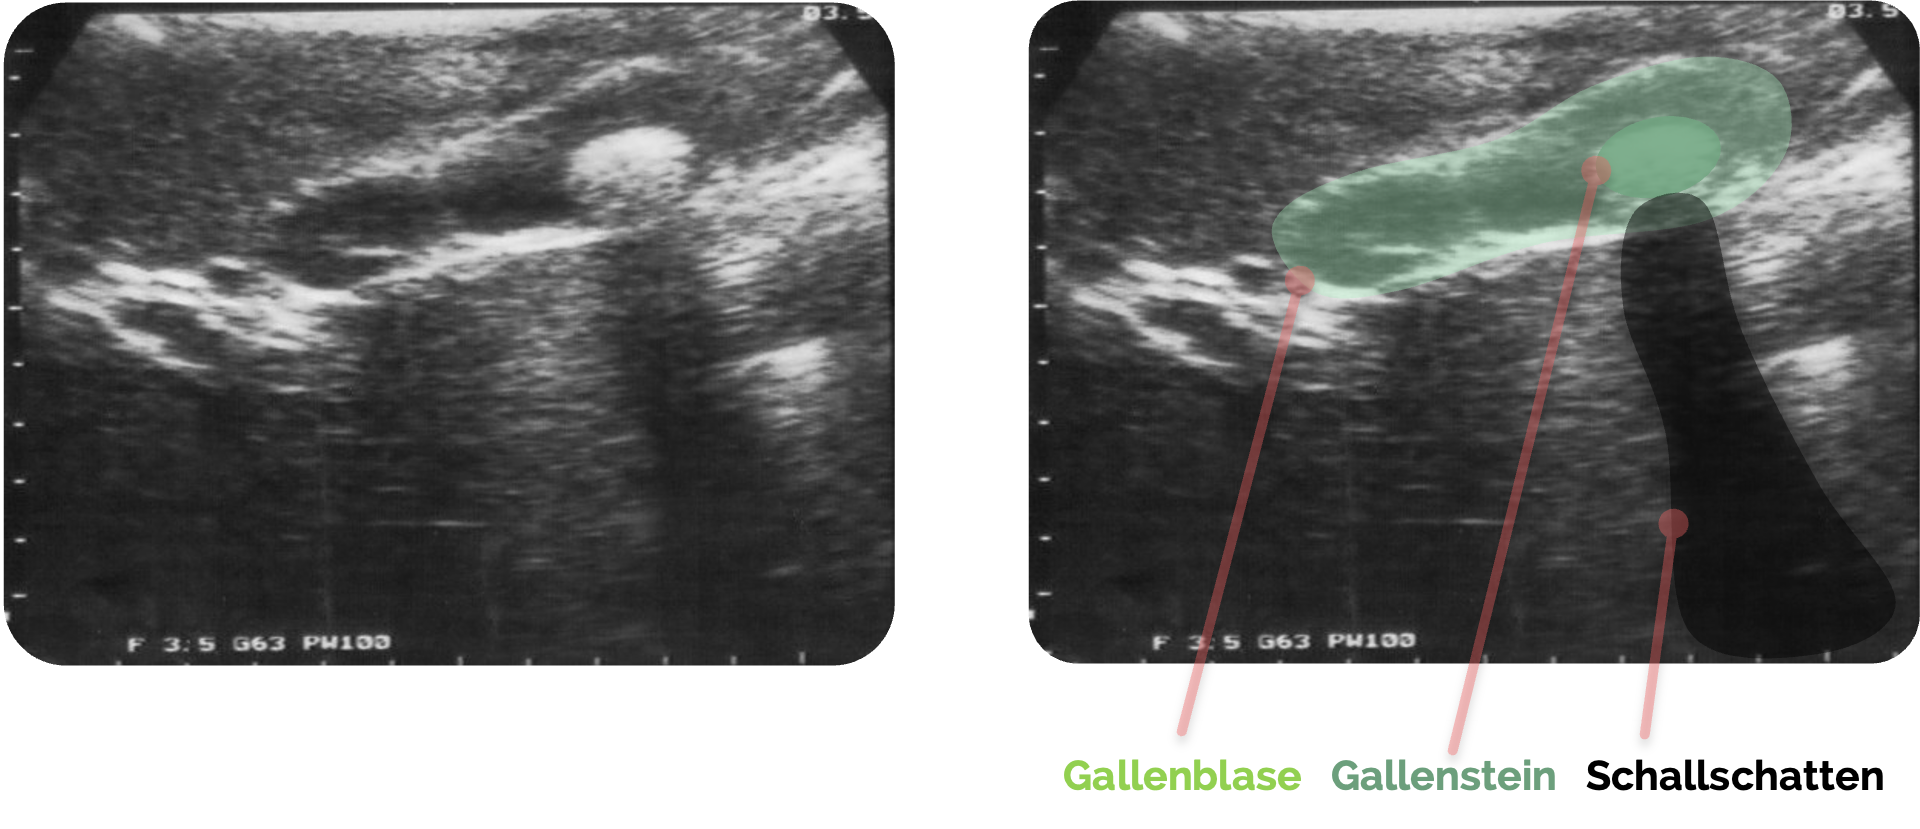

Schallschatten:

Ein Schallschatten suggeriert, dass hinter einer Struktur keine weiteren Informationen erfasst werden können. Das Prinzip entspricht einem Lichtstrahl, der auf ein Hindernis trifft. Bei dichten Strukturen wie Knochen wird der eintreffende Schall nahezu vollständig absorbiert oder reflektiert, sodass kein Signal in die tiefer liegenden Bereiche gelangt. Es entsteht ein „blinder Bereich“ im Bild. Typische Beispiele sind die Rippenbögen, die den Einblick auf darunterliegende Organe erschweren. Gleichzeitig kann ein Schallschatten jedoch diagnostisch wertvoll sein, etwa bei Gallen- oder Nierensteinen sowie bei Fremdkörpern, da diese Strukturen charakteristische artifizielle Schatten erzeugen.

Schallschatten der Rippen links und rechts der Bildmitte